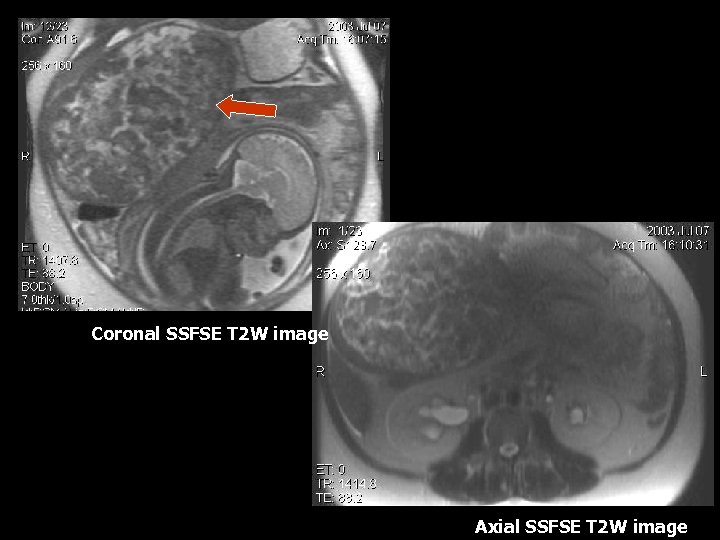

Coronal SSFSE T 2 W image Axial SSFSE T 2 W image

Large Leiomyoma • 25 -50% of women of child bearing age(6). • Composed of smooth muscle and variable amount of fibrous tissue, surrounded by a psuedocapsule of areolar tissue (6). • Hormonal stimulation due to pregnancy can cause rapid growth(6). • MRI findings: T 2 W images demonstrate a well circumscribed mass with predominantly low signal intensity (6). • T 1 weighted images show intermediate signal, often indistinguishable from surrounding uterine tissue(6). • Degenerative changes appear as high signal on T 2 weighted images(6). • Foci of calcifications appear as low intensity on all sequences (6).